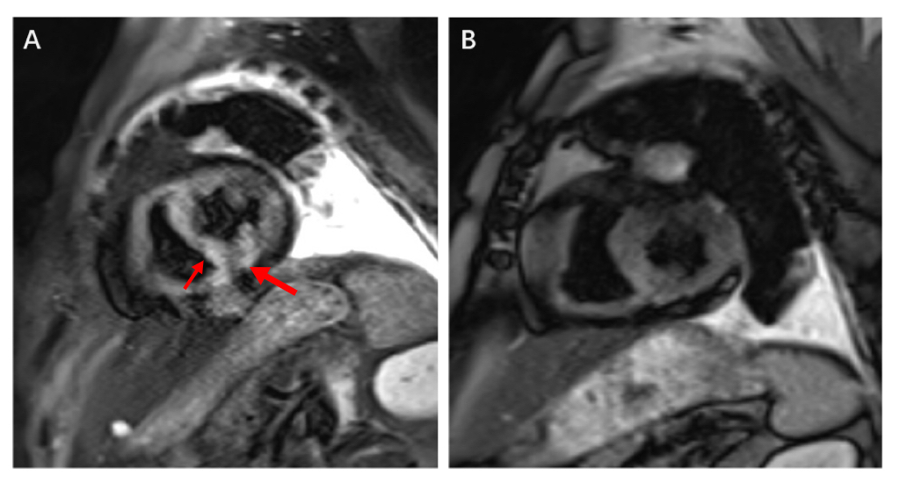

邓阿姨是“入住”过心胸整合病房的患者,她与肿瘤的抗争已持续近十年。但在一次常规治疗前,她的心肌肌钙蛋白突然显著升高,还出现了严重的室性早搏和室速!心脏一半时间都在“乱跳”,随时可能恶化为室颤或心脏骤停。韩文正副主任凭借丰富经验,迅速锁定元凶,是免疫检查点抑制剂相关性心肌炎,十分罕见但致死率极高!团队立即针对性地进行大剂量激素冲击治疗,用药第二天患者的心肌酶就开始回落,六周后心脏磁共振显示心肌水肿已基本消失。现在,邓阿姨仍继续在医院接受后续的抗肿瘤治疗,病情平稳。

图A 患者心肌水肿明显。 图B 出院后6周随访心肌水肿明显消退